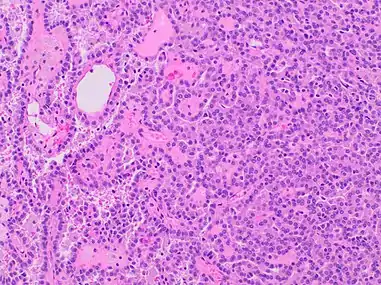

| Papillary renal cell carcinoma, type 1, characterised by tubulopapillary architecture with admixed foamy histiocytes in the papillary cores. | |

A micrograph of type 1 PRCC, illustrating features of small basophilic cells with scarce cytoplasm. A single layer of cells are surrounding the basal membrane.[20] Foamy macrophages are inside of papillary fibrovascular cores.